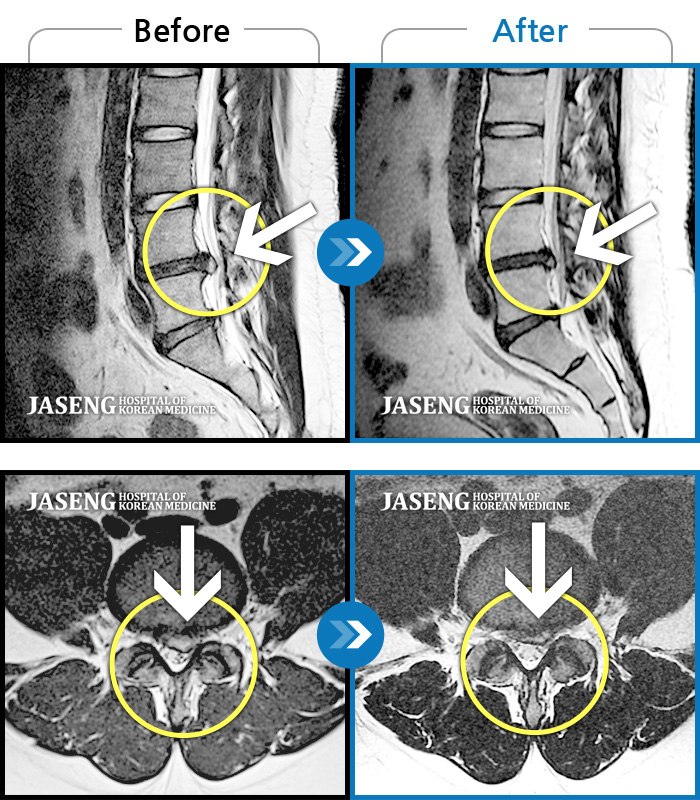

허리디스크

일산 · 김태용 원장

허리와 좌측 다리가 당겨 보행이 불가능했다.

촬영시기

2020.02.10 ~ 2021.02.22

2021.02.26